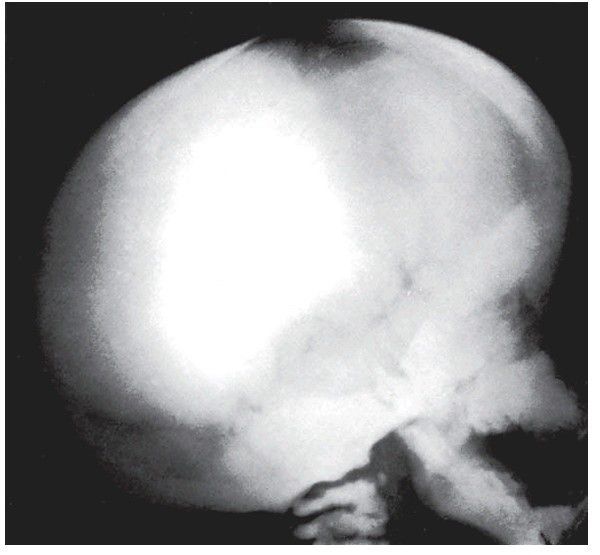

Osteopetrosis

. In contrast to osteogenesis imperfecta the bone is excessively thick and dense as a result of defective resorption.